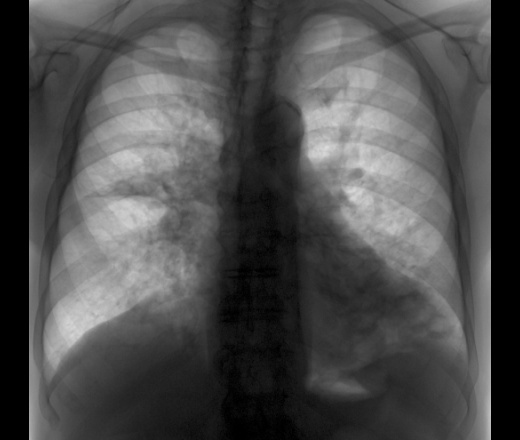

Дедушка с бронхоэктатической болезнью

Пришел дедушка на флюорографию. Подняла предыдущую флюшку.

Снимок за 26.06.09 Снимки 05.03.10

Очень смущает 3 сегмент.

Ваше мнение?

Много всякой всячины, но к S3 спрва нужно присмотреться.